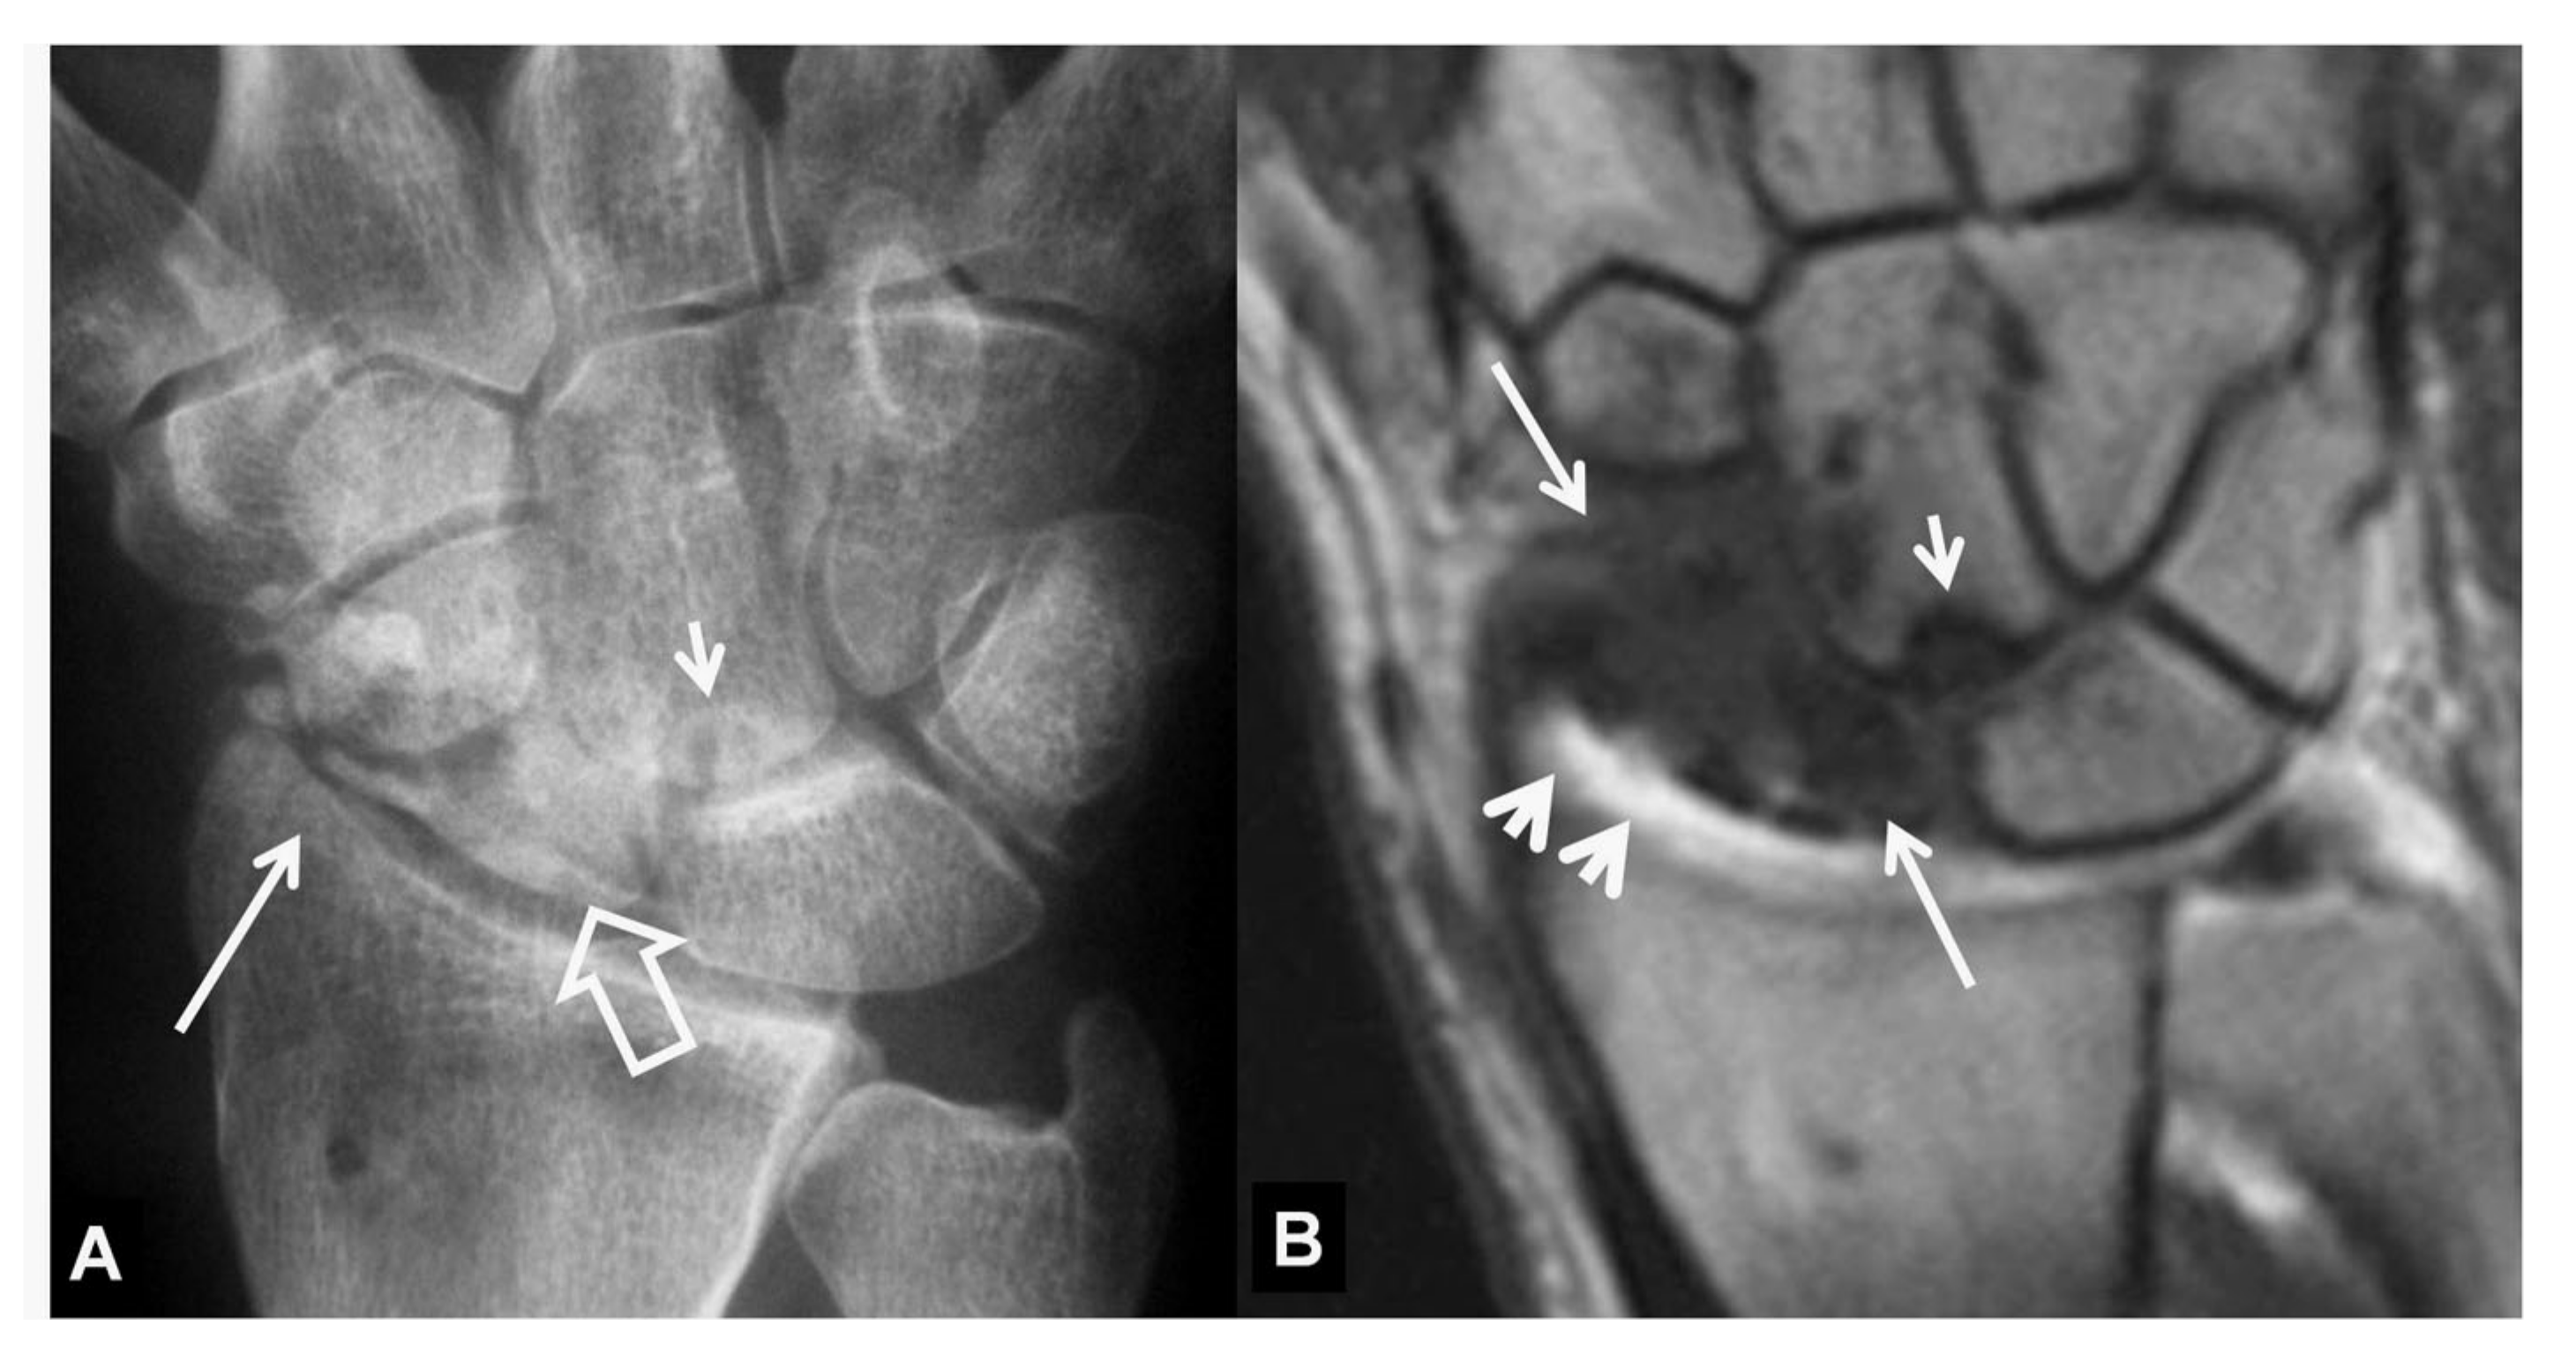

Figure 13.

A 41-year-old male patient with a scaphoid fracture 5 years prior to current imaging and persistent pain and functional impairment during the last 2 years. (A) PA radiograph showing proximal pole osteosclerosis in keeping with osteonecrosis (open arrow) and radial radioscaphoid joint space narrowing with minimal subchondral sclerosis in keeping with SNAC stage I disease (arrow). (B) Coronal T1w MR arthrographic image showing irregularity of the radioscaphoid space (arrowheads) and low signal intensity of the scaphoid bone marrow suggesting global osteonecrosis (arrows). Subchondral sclerosis suggesting early osteoarthritis is shown on both images in the proximal capitate (small arrows).